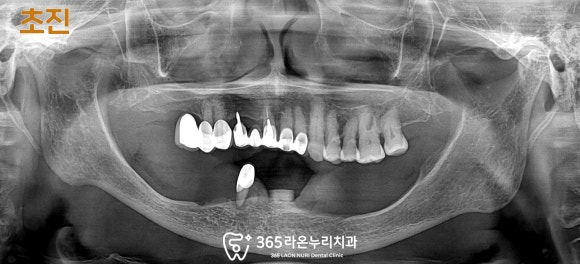

■ 1. 초진

“전체 틀니를 하거나 임플란트 하고 싶어요.

밥 먹는 게 너무 힘들어요.”

위와 같은 주소(c.c)로

찾아오신 환자입니다.

구강을 살펴보면

그간 남아있는 아랫니 단 하나의 치아에

부분틀니(patial denture)를 걸어

사용하고 계셨습니다.

그런데 틀니는 아무래도

식사를 하실 때마다 들썩거리며

잇몸을 지속적으로 짓누르다 보니

통증도 심하셨고

계속되는 스트레스로 인하여

실제 잇몸뼈(치조골)는 매우 얇아져있습니다.

제가 초록색으로 표시해 둔 곳이

정상 치조골 두께인데,

이 케이스에서는 치조골의 폭(빨간색 표시)이

상당히 좁고 얇아져있죠?

이가 빠지고 오래되면 치조골의 흡수가 일어나고

틀니를 오래 사용하다 보면 치조골이 내려앉거나

약해지면서 위와 같은 모습으로 변하게 됩니다.

상악은 비교적 양호한 상태였으나

아무래도 위아래 균형이 맞지 않다 보니

식사하는데 많이 힘드셨을 것 같습니다.